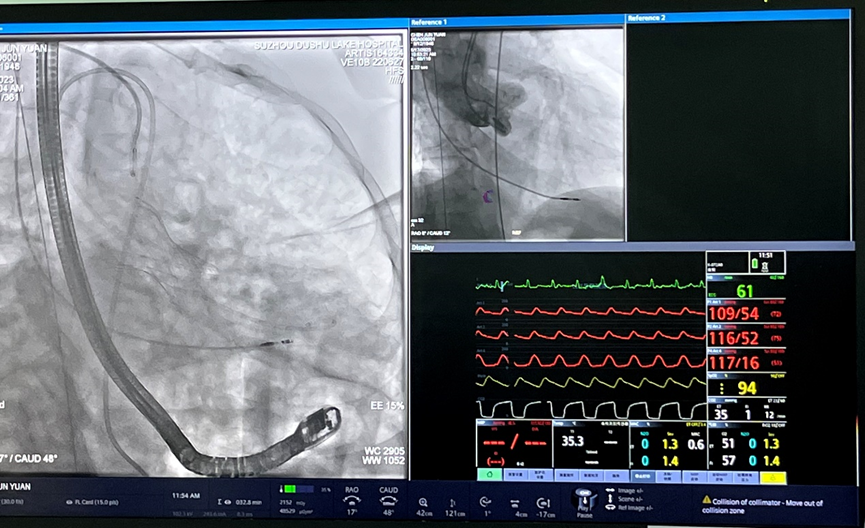

患者为74岁男性,因“反复胸闷1年余,加重1周”入住我院心内科病房。入院后完善心脏彩超,根据结果诊断为主动脉瓣重度狭窄。此次手术选用园区某生物医药公司自研的瓣膜,术前跨瓣压差测得68mmHg左右,术后即刻跨瓣压差小于5mmHg,手术效果较好。

本次TAVR手术所使用的瓣膜为园区某生物医药公司自主研发的经导管主动脉瓣系统,为二代可回收瓣膜,在提高TAVR手术安全性的同时,缩短术者学习曲线。我院期望将自身学科优势、技术优势与园区生物医药产业优势相结合,积极响应我国新医科“医工结合”、服务健康中国的理念,推动企业更快地将创新产品向临床转化。未来,医院将继续充分利用自贸区内生物医药产业的集群优势和政策利好,围绕新兴诊疗器械、创新药物、创新疗法及体外诊断试剂等方向,与企业共同产出一批有重大产业化价值的成果,促进相关学科的高质量发展。